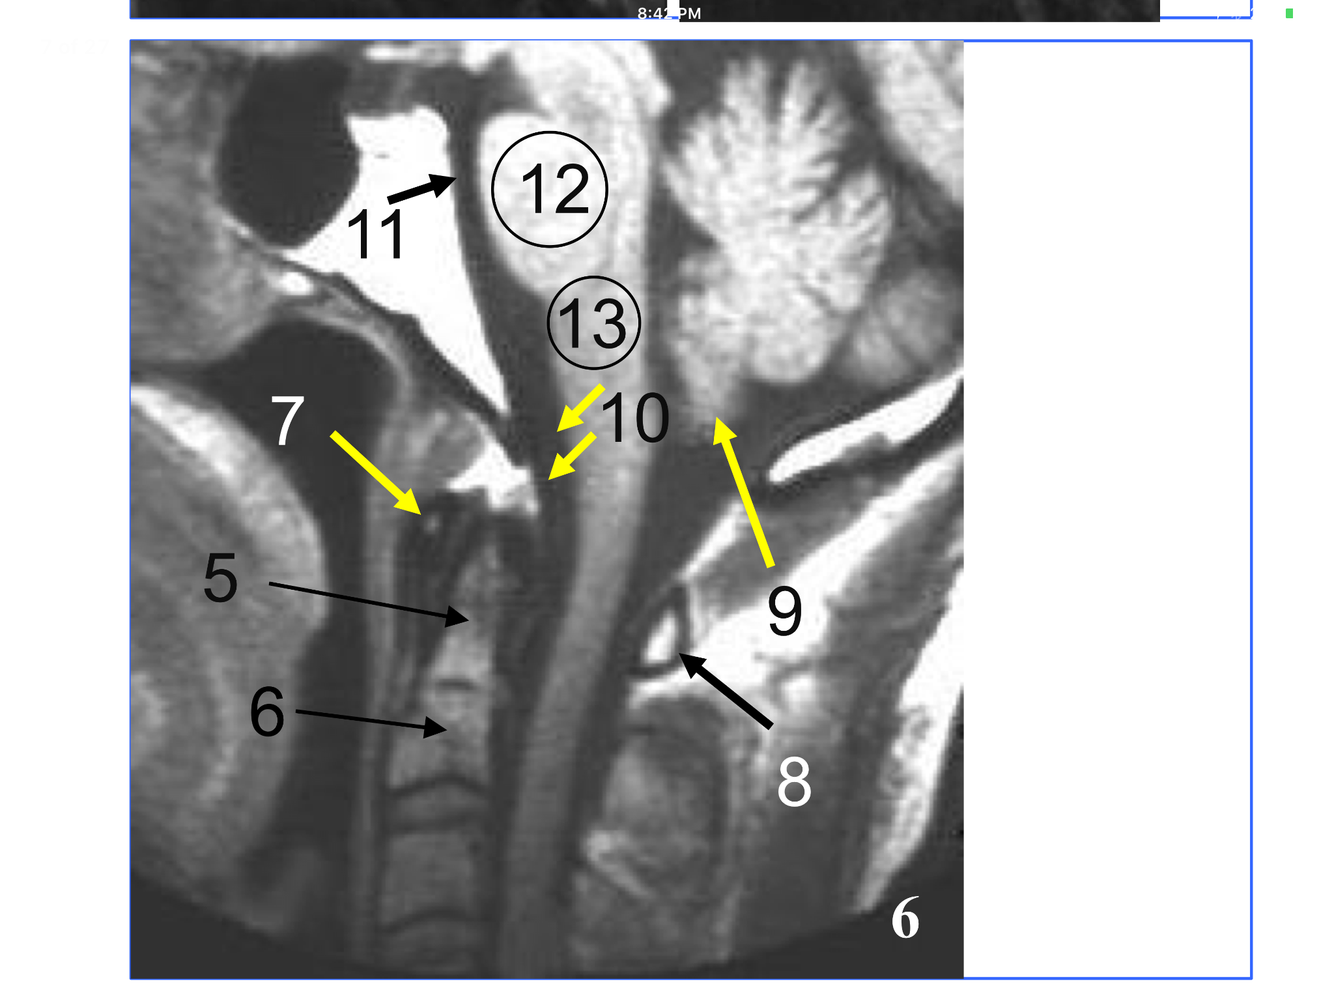

*Comprised of the inferior and superior articulating processes, and the zygapophyseal joints they form

**10. Rt & Lt vertebral arteries**

*Although the transverse process is not seen, the tubercle articulates with the transverse costal facet on it.

*Immediately above the conus, which is at L1-L2